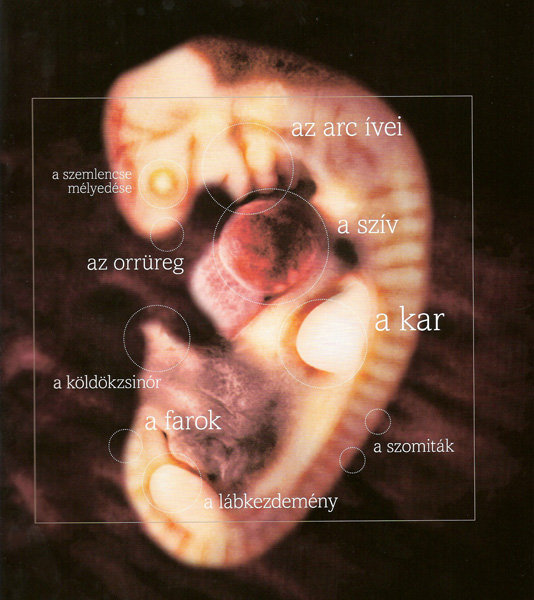

Annus nagyon jók a képek. kis ALien-nek néznek ki... szép az élet...

5mm a baba  8 mm a baba

8 mm a baba  11 mm a baba